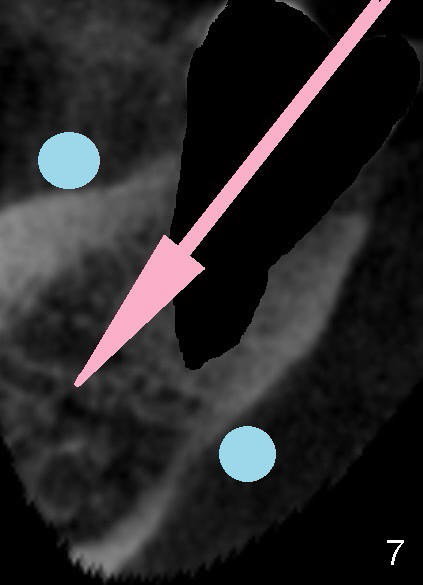

Fig.5 is an illustration, showing the socket after extraction (from Fig.1). The red circle in Fig.5 represents the lingual artery, which is the 2nd branch from the external carotid artery. When the lingual artery is severed by an overdrilling bur, it shrinks toward the external carotid artery. Hemostasis is difficult to achieve without emergency surgery. Failure to recognize the proximity of the lingual concavity may lead to perforation of the lingual plate while osteotomy is forming (Fig.6 red arrow) and potentially damage the lingual artery in the submandibular fossa. Although CBCT is essential for recognition of this special anatomy, a surgical technique is the most critical step to avoid the injury. That is to use two fingers (Fig.7 blue circles) to hold the buccal and lingual plates as low as possible and let the tactile sense guide you and keep the osteotomy in the middle of the ridge (pink arrow). One of the fingers may sense the vibration before perforation of the lingual plate. Use a long explorer to probe the osteotomy site after each bur. A surgical stent is also helpful. If an immediate implant is placed, the osteotomy should be initiated in the buccal wall of the socket of the 2nd molar (Fig.7). For the 1st molar of this case, the osteotomy is to be placed slightly lingual (Fig.8 (an illustration from Fig.2) pink arrow), since the buccal bone is lower than the lingual (Fig.2 <) and especially on the affected side (root fracture) (Fig.3).